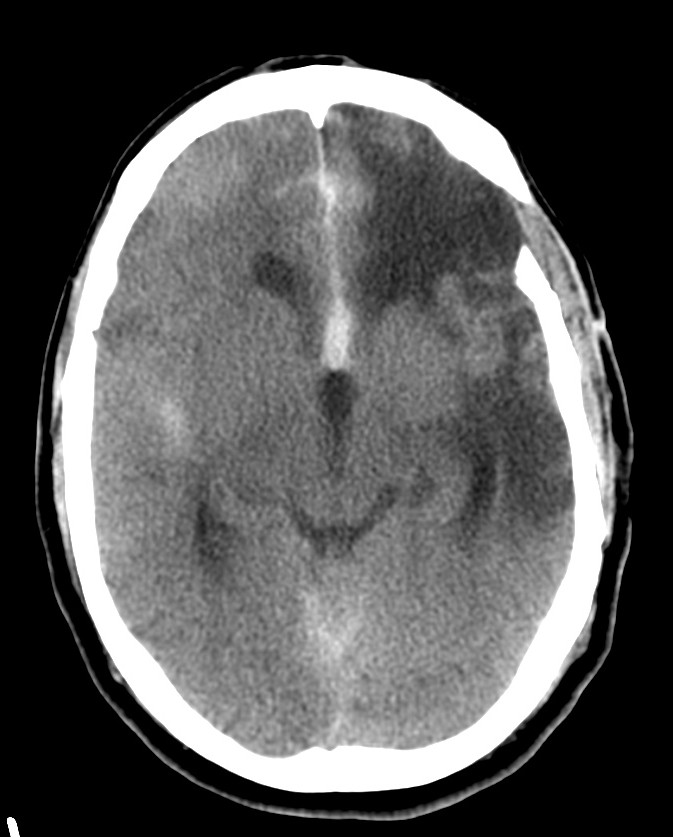

Paciente de 58 años que acude a urgencias con pérdida de conciencia y que, según un familiar, se quejaba de una cefalea «muy insoportable», de inicio súbito y que comenzó hace 20 minutos aproximadamente.

TA 175/100; FC 105; Sat 02 96%.

Se realiza TC de cráneo sin contraste, objetivándose:

Estamos ante una Hemorragia Subaracnoidea por rotura aneurismática.

Aunque la RM tiene mayor sensibilidad para el diagnóstico de sangrado, es la TC la prueba de primera línea debido a su mayor disponibilidad. Observaremos la característica imagen de hiperdensidad en las cisternas basales que corresponde a la sangre extravasada. La mayoría de las veces veremos el característico aumento de densidad alrededor del polígono de Willis (65%), que es donde ocurren la mayoría de las roturas de aneurismas, y también en la región de la cisura de Silvio (30%). Podemos ver también sangre en la fosa interpeduncular o asta occipital de los ventrículos laterales.

La TC ayuda a distinguir la ruptura aneursimática espontánea del sangrado tras traumatismo. Si la causa es un trauma, veremos el sangrado subaracnoideo confinado a los surcos superficiales de la convexidad del cerebro adyacente a la zona de fractura o contusión parenquimatosa. No obstante, si el traumatismo es en la región frontal, podemos ver sangre que simula una ruptura de aneurisma de la arteria cerebral anterior y cuando hay sangre en la cisura de Silvio o Ambiens, puede ser difícil distinguir entre traumatismo y aneurisma roto. Si el traumatismo es sobre el cuello, puede originarse un sangrado masivo que afecte las cisternas basares por afectación de las arterias de la circulación posterior.